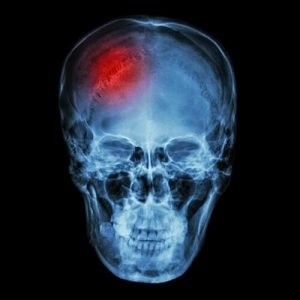

- рентгенологическое исследование черепа;

- компьютерную томографию;

- магнитно-резонансную томографию;